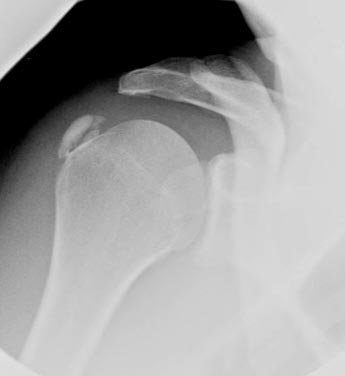

© La Revue du Praticien Radiographie d'épaule droite de face. Volumineuse calcification ovalaire sur le trajet du tendon supra-épineux.